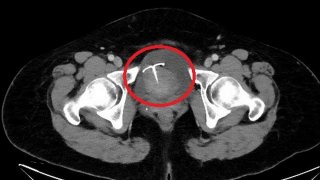

หญิงวัย 55 ปี มดลูกทะลุ พบห่วงอุปกรณ์คุมกำเนิดทำพิษ

สื่อนอกรายงานว่า "หญิงวัย 55 ปี มีอาการปวดท้องอย่างหนักและต่อเนื่อง ซึ่งเธอได้ตัดสินใจมาหาหมอที่โรงพยาบาลเพื่อรักษา เนื่องจากเธอทำทุกวิถีทางแล้ว อาการปวดท้องก็ไม่ได้บรรเทาขึ้นเลย หลังจากนั้นแพทย์จากแผนกสูติ ของโรงพยาบาลในกรุงไทเป ประเทศไต้หวัน ก็ได้ทำการตรวจอัลตราซาวนด์ ซึ่งแพทย์ก็พบว่าสาเหตุของอาการปวดท้องของเธอ มาจากอุปกรณ์คุมกำเนิด แบบทองแดง ที่อยู่ภายในร่างกายเธอ มานานกว่าสิบปี อุปกรณ์คุมกำเน.. ดูเพิ่ม